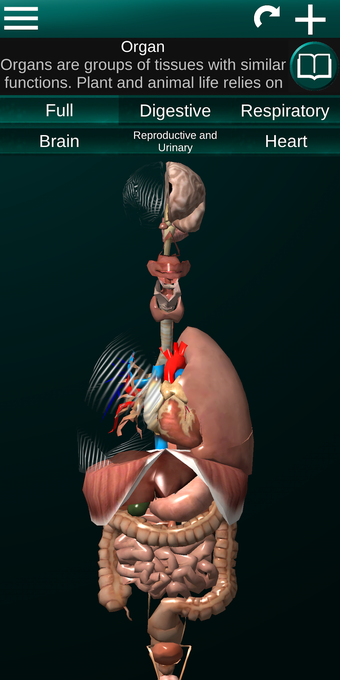

Diese Anwendung zeigt ein dreidimensionales Modell der menschlichen Körperorgane und eine Beschreibung aller von ihnen.

Sie können jedes Organ wie Herz, Gehirn, Lunge, Fortpflanzungssystem, Leber, Darm, Eierstock, Hoden, Magen, Niere usw. anfassen.

Die Anwendung soll das Studium der Anatomie in Medizin, Biologie oder anderen Fächern ergänzen.

Sie ist für alle Menschen nützlich, auch für Studenten, da jedes Anatomieorgan in einer anderen Farbe dargestellt ist.